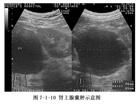

白細胞記數和中性粒細胞分類常明顯增高。尿常規正常,但腎周膿腫時可有膿尿、蛋白尿和菌尿。X線腹部平片可在受累側顯示一軟組織塊影,腎影模糊不清和腰大肌邊緣模糊,有時見膿腫處有氣液平,脊柱彎曲,腸麻痹。也可見腰椎或肋骨破壞,橫膈抬高,胸腔積液。鋇餐檢查可發現鋇外流入膿腔,從而發現瘺管或竇道。B超及CT檢查可明確發現腹膜後積液,必要時可在B超定位或引導下細針穿刺抽液,可明確診斷。